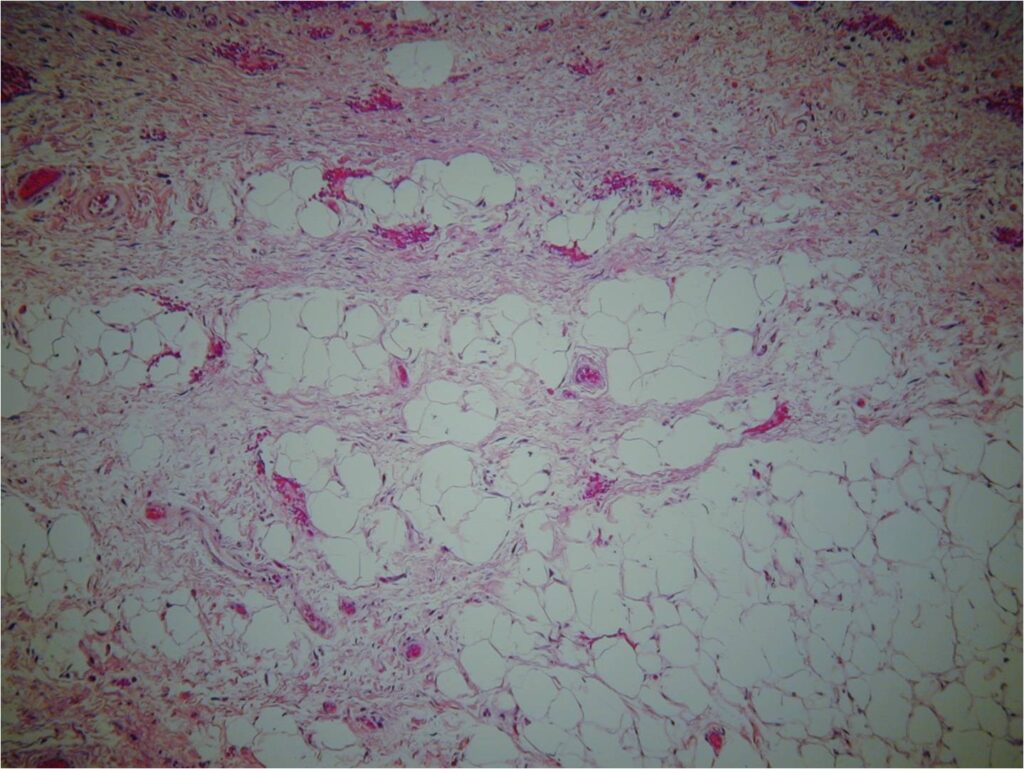

Microscopic Pathology (Fig. 6, 7, 8)

• Atypical stromal cells and lipoblasts in the context of mature fat

• Lipoblasts are immature fat cells often with a bizarre displaced nucleus (the nuclei of benign fat cells are usually very thin and displaced to periphery of cell membrane)

• Often with a prominent fibrous component

• The fat cells are often different sizes and shapes

• Genetic marker and ring chromosomes (12q13-15)

• Overexpression of oncogenes MDM2 and CDK4 (positive IHC for those markers).

Fig. 6-8 Microscopic Pathology. Low (Fig. 6), medium (Fig. 7) and high (Fig. 8) magnification H & E slides. Atypical stromal cells and lipoblasts in the context of mature fat. Often with a prominent fibrotic component and stranding. Higher magnification shows disorganized stromal cells and hyperchromasia of nuclei.